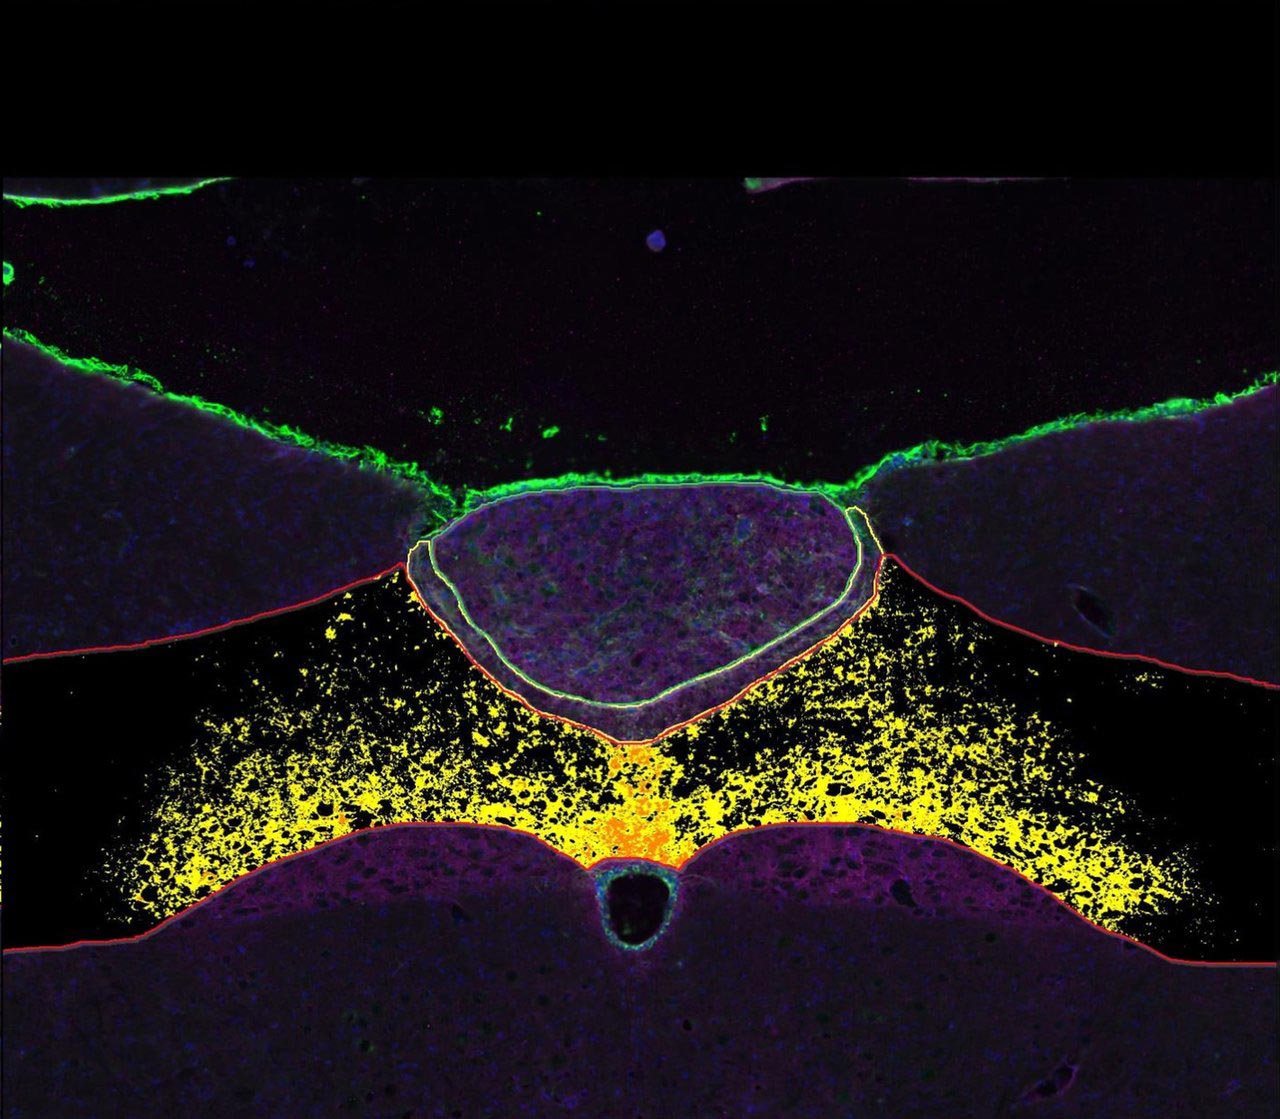

Working with colleagues at the University of Pennsylvania and the University of Kentucky, Doyle helped identify a chemical produced by astrocytes that could open the door to future appetite-control drugs with fewer side effects. Their findings were published in Science Translational Medicine.

The research team discovered that some support cells in the hindbrain naturally produce a molecule named octadecaneuropeptide (ODN), which suppresses appetite. In lab tests, injecting ODN directly into rats’ brains made them lose weight and improved how they processed glucose.

However, injecting directly into the brain isn’t a practical treatment for people, so researchers created a new version of the molecule named tridecaneuropeptide (TDN). This molecule version could be given to human patients through regular injections akin to today’s Ozempic or Zepbound. When tested in obese mice and musk shrews, TDN helped the animals lose weight and respond better to insulin without causing nausea or vomiting.